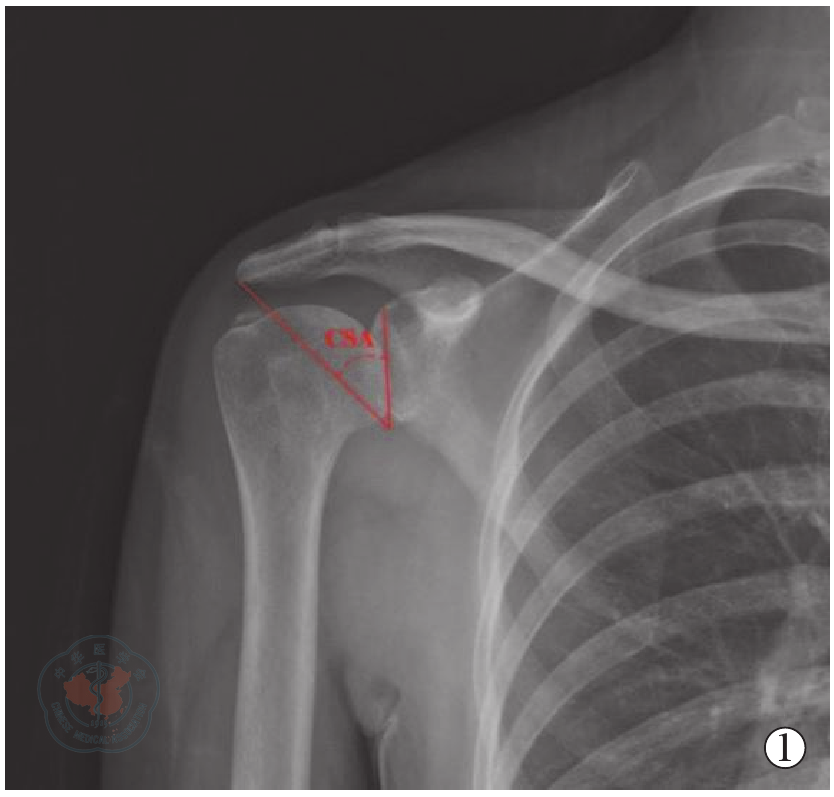

图1 CST(肩袖钙化性肌腱炎)组CSA(肩关键角)测量方法示意图

Figure 1 Schematic diagram of measurement method for CST group CSA